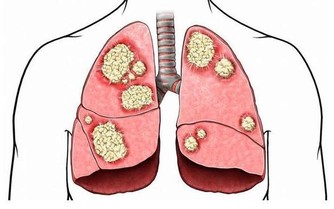

食物經過燒烤不但會損失脂肪和蛋白質等營養成分,還容易產生致癌物。

酒精會擴張消化道血管,並破壞消化道黏膜,使這些致癌物質更易被人體吸收。